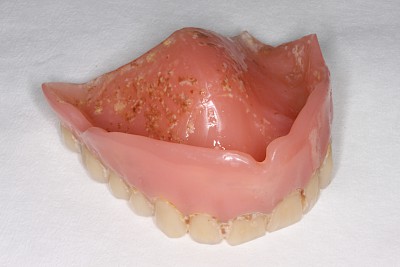

Weichbleibende Unterfütterung

Weichbleibende Unterfütterungen werden durchgeführt, wenn es immer wieder zu Prothesendruckstellen kommt. Allerdings lassen sich weichbleibende Unterfütterungsmaterialien nicht so gut reinigen. Es kommt schneller zu Belagsbildungen und Pilzbefall. Mit der Zeit können zudem die Materialien verspröden, was die Belagsbildung weiter begünstigt. Dann spätestens ist es sinnvoll und notwendig, den Zahnarzt zu verständigen.